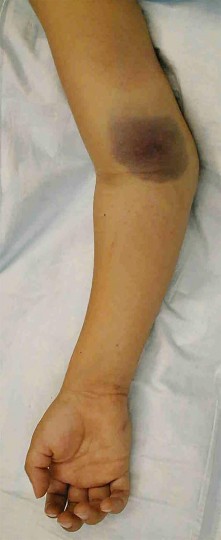

A 7-year-old boy undergoes closed reduction and percutaneous pinning of a displaced supracondylar humerus fracture.

Six hours postoperatively, he is crying uncontrollably on the ward and requires escalating doses of IV opioids. Which of the following is the most reliable early clinical indicator of compartment syndrome in this pediatric patient?